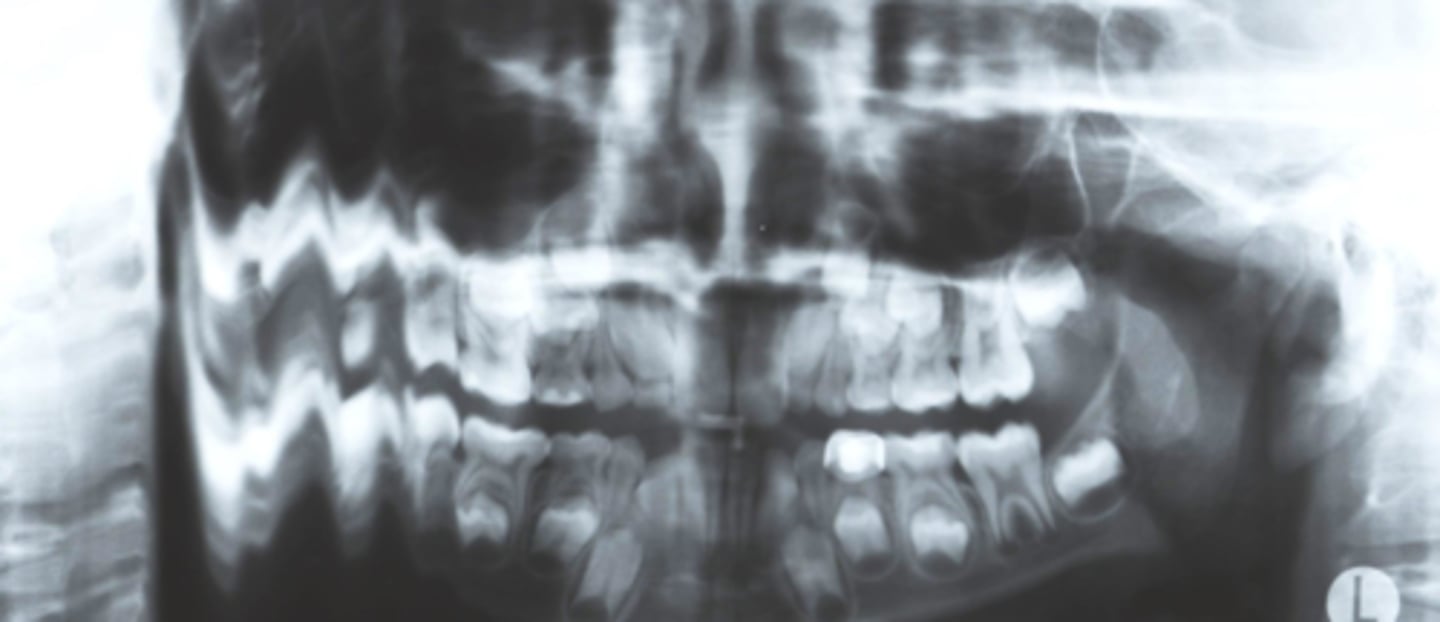

B) Frankfort plane

What light needs to be repositioned in order to fix the flatness seen in this image?

A) mid-sagittal

C) focal trough

A) up

The chin was slightly ___, resulting in this image

B) down

What light needs to be repositioned in order to fix the curve of the smile?